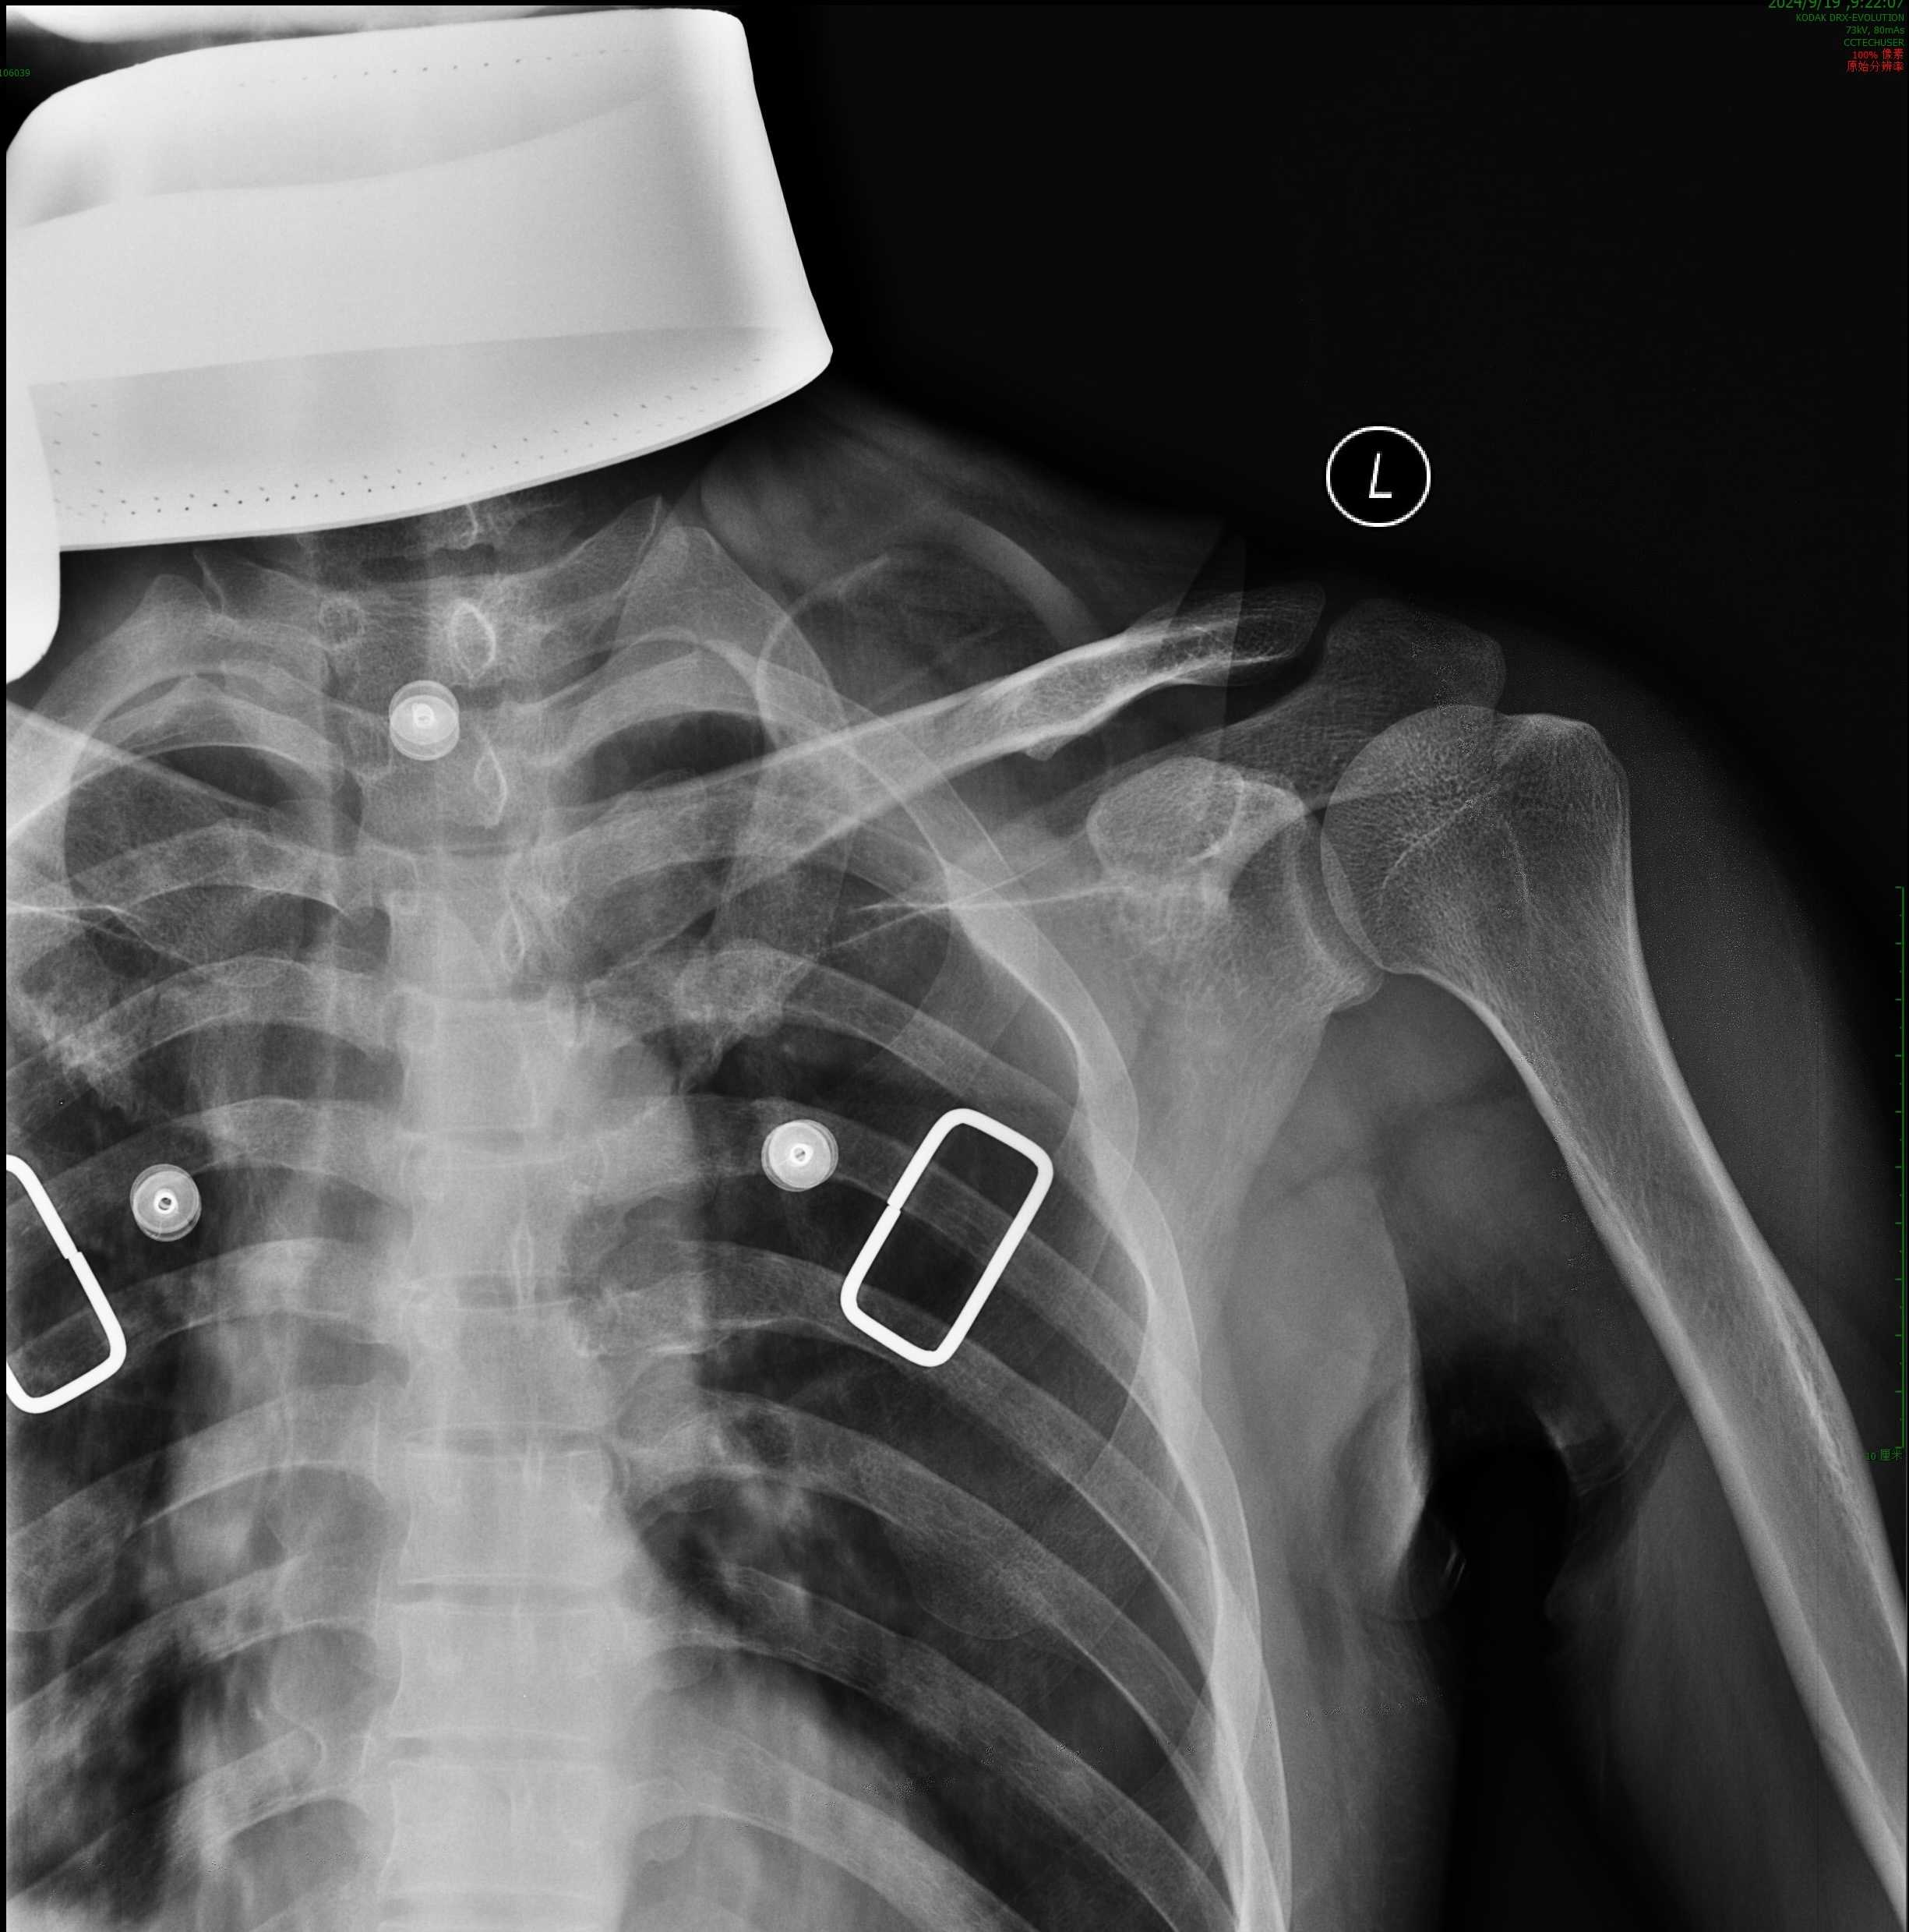

复位固定后

手法正骨二科主诊组长赵朝锋通过医工结合的方式,采用智能算法模拟手法复位,并设计3D打印定制外固定导板和压垫,为患者进行精准手法复位,用定制导板辅助外固定,贴附性能好,固定牢靠,定制压垫在控制骨折近端移位的同时还能避免皮肤压伤。通过数字骨科技术和中医骨伤手法复位技术结合,充分发挥了中医简、便、验、廉的优势,达到不手术、不穿针、不出血的精准复位和牢靠固定目的,使患者在我院得到优质医疗服务。

通过手法复位,利用锁骨带固定的非手术方法治疗锁骨骨折,难点在于复位时效果良好,但难以维持有效固定,往往固定一周后拍片复查,会出现近折端向上移位现象。利用数字骨科3D打印技术,将锁骨近端皮肤外加一块3D打印的导板压垫,可有效阻止近折端上移,从而使骨折端达到精准和有效的固定,减轻患者痛苦,避免二次手术,减少患者医疗支出。